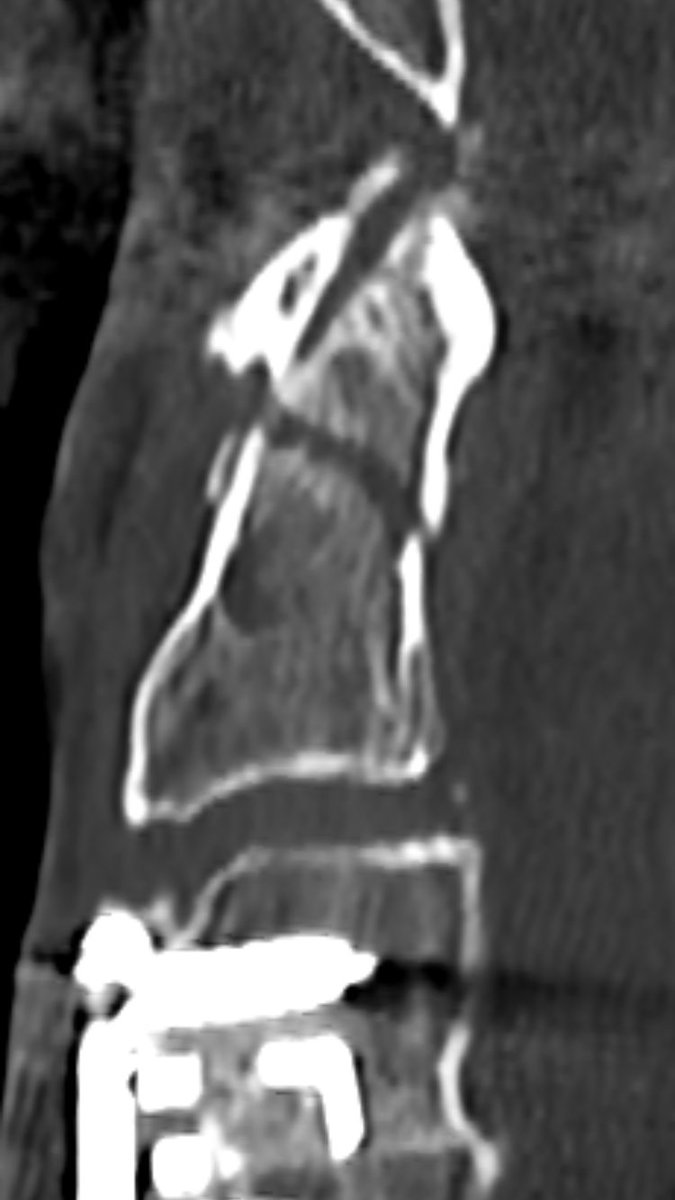

4 years later (after ACDF), he fell and sustained odontoid fracture type II according to Anderson/d’Alonzo. you see the fracture line - and no, it’s not “incomplete”, it’s for sure complete, just the positioning in the CTscan. As pain was no problem, we’ve put him in a collar

follow up after 8 weeks (l) and 6 month (r) show non-union, as expected. It’s a pseudarthosis.

You can nicely see signs of remodelling, but the fracture line still remains.

after 16 month, remodelling is still ongoing: surprisingly the atlantodental joint is now ankylosed and the fracture line is narrowed, but still not fused.

(CT was performed for other reason)